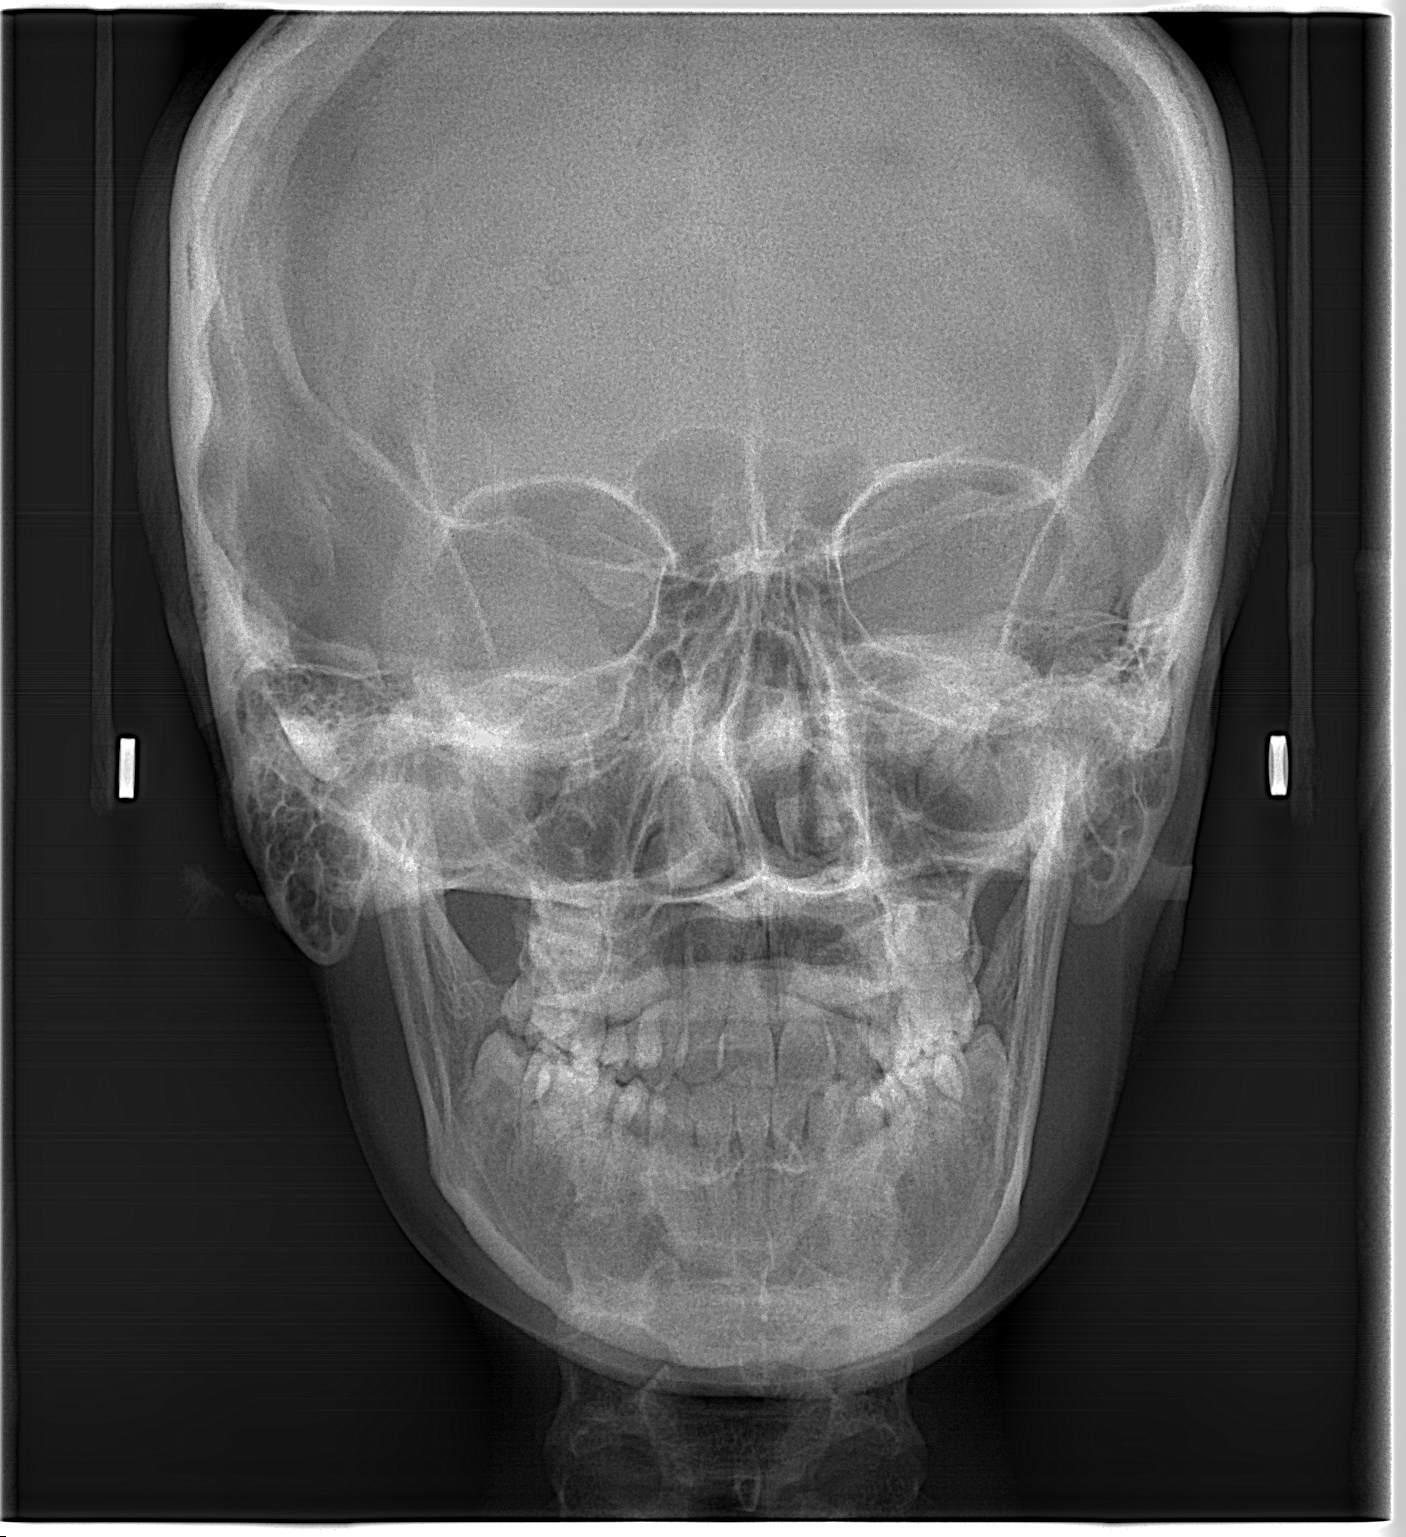

- Radiografía AP y PA: Radiografía utilizada para evaluar principalmente asimetrías faciales, seno frontal y etmoidal, fosas nasales y orbitas.